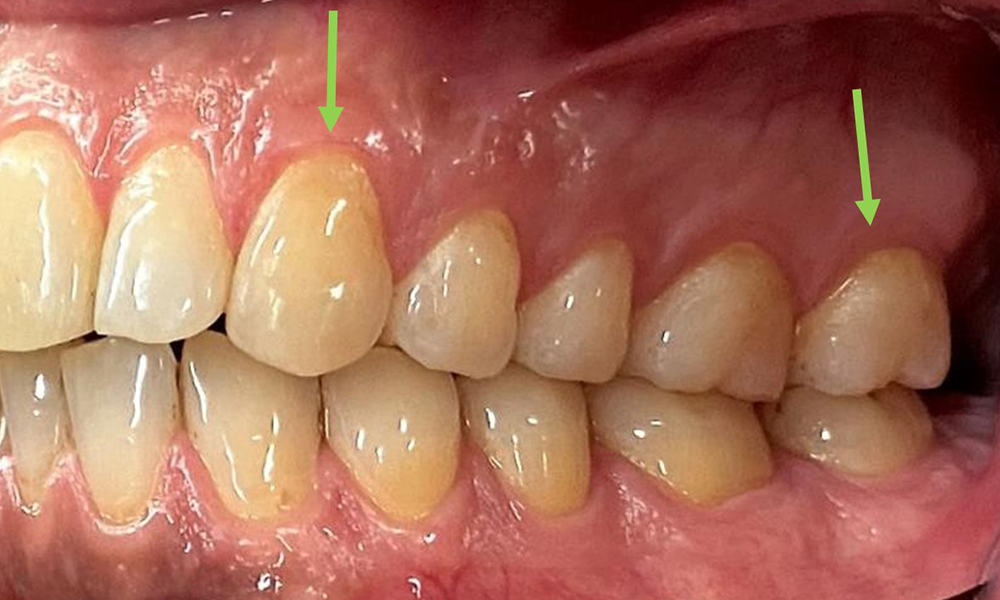

Няма патологични екстраорални резултати. По време на интраоралния преглед се установи кафеникаво оцветяване в близост до кератинизираната гингива и при прехода към подвижната лигавица (фиг. 2), което може да се отдаде на консумацията на никотин. В областта на небцето, особено в близост до небцовите повърхности на максиларните молари, се наблюдават белезникави лезии на лигавицата, които показват повишена кератинизация и също могат да се припишат на консумацията на никотин. Езикът е покрит с бяло-кафеникаво покритие, което може да се отстрани.

Клиничните дълбочини на сондиране от 1 до 3 мм са във физиологичния диапазон. От 13 до 16 и от 23 до 27 се наблюдават максиларни рецесии до 1 mm. BOP е 15 %.